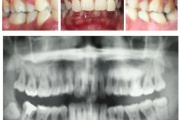

Luukadu agressiivse parodontiidiga patsiendil